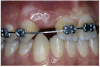

The 3.7-mm diameter Tapered Screw-Vent implant drilling sequence required three drills: pilot, intermediate, and final sizing. Thus, three separate templates were fabricated to accommodate these sizes. The templates were removed easily and replaced with the next sequential size in less time than it takes to change the drill on the surgical handpiece. After the osteotomies had been completed, the implants were delivered to the site (Figure 16A and Figure 16B). For this internal hex connection implant, the author r.commends that the flat of the antirotational hex be positioned to the facial for proper orientation of the restorative components (Figure 17A). Preprepared margins were created from a milled titanium fixture mount transfer post, which was delivered to the implant as support for an immediate transitional restoration. The facial “dot” helped confirm the orientation of the abutment to the facially positioned flat side of the internal hex connection (Figure 17B). Before cementation of the transitional acrylic restorations, a closed-tray, fixture-level impression was made, and a soft-tissue model fabricated.

Figure 16a  After (A) the osteotomies were completed, (B) the implants were placed.

Figure 16a

Figure 16b  After (A) the osteotomies were completed, (B) the implants were placed.

Figure 16b